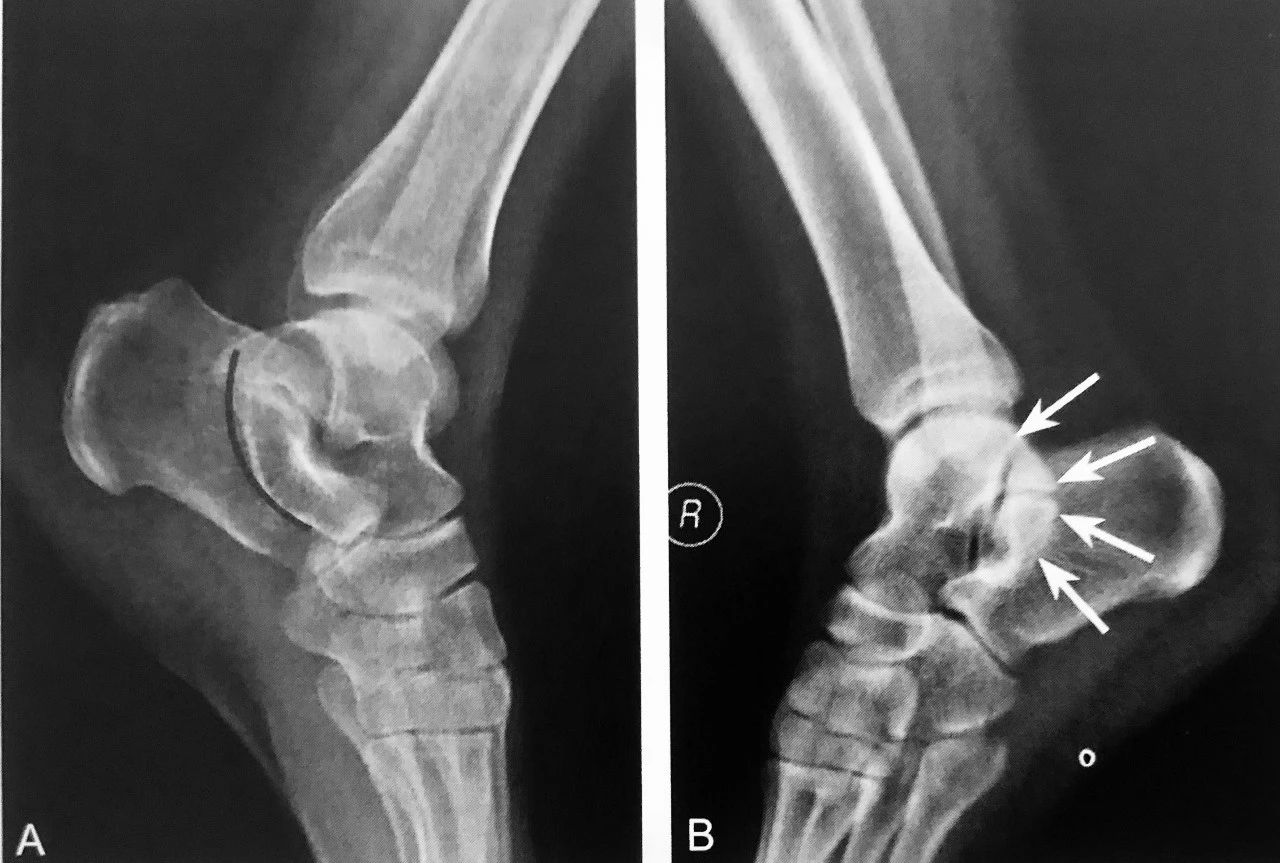

双 弧 征

双弧征:A 图正常肘关节侧位 X 线图;B 图患者肘关节 ⅹ 线侧位片示肱骨远端可见两个弧形:一个弧提示肱骨小头游离(细箭头),另一个弧是肱骨滑车游离(粗箭头),双孤征提示肱骨远端冠状面 Dubberley Ⅲ 型骨折;C.同一患者肘关节 Ⅹ 线正位片可见肱骨小头骨皮质不连续(细箭头),肱骨滑车可见线状透亮影(粗箭头);D.CT 的VR 图像可见肱骨远端肱骨小头-滑车骨折

判读要点:

1、肱骨远端冠状面骨折,即肱骨小头-滑车骨折的直接征象;

2、在肘关节侧位片或通过 CT 多平面重建观察;

3、诊断肱骨远端冠状面骨折阳性预测值较高,敏感度相对稍低;4、肱骨小头-滑车骨折应做到手术解剖复位,否则影响预后。